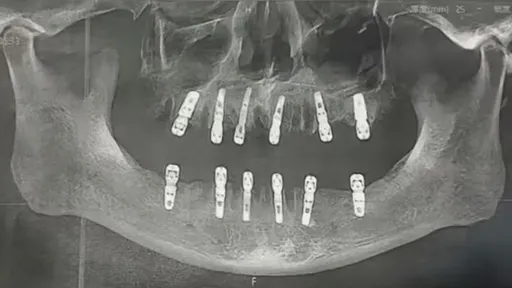

...出,父親於8月14日到永康德維口腔醫院拔牙23顆、植牙12顆,術後疼痛不已並導致父親十餘天後過世,目...